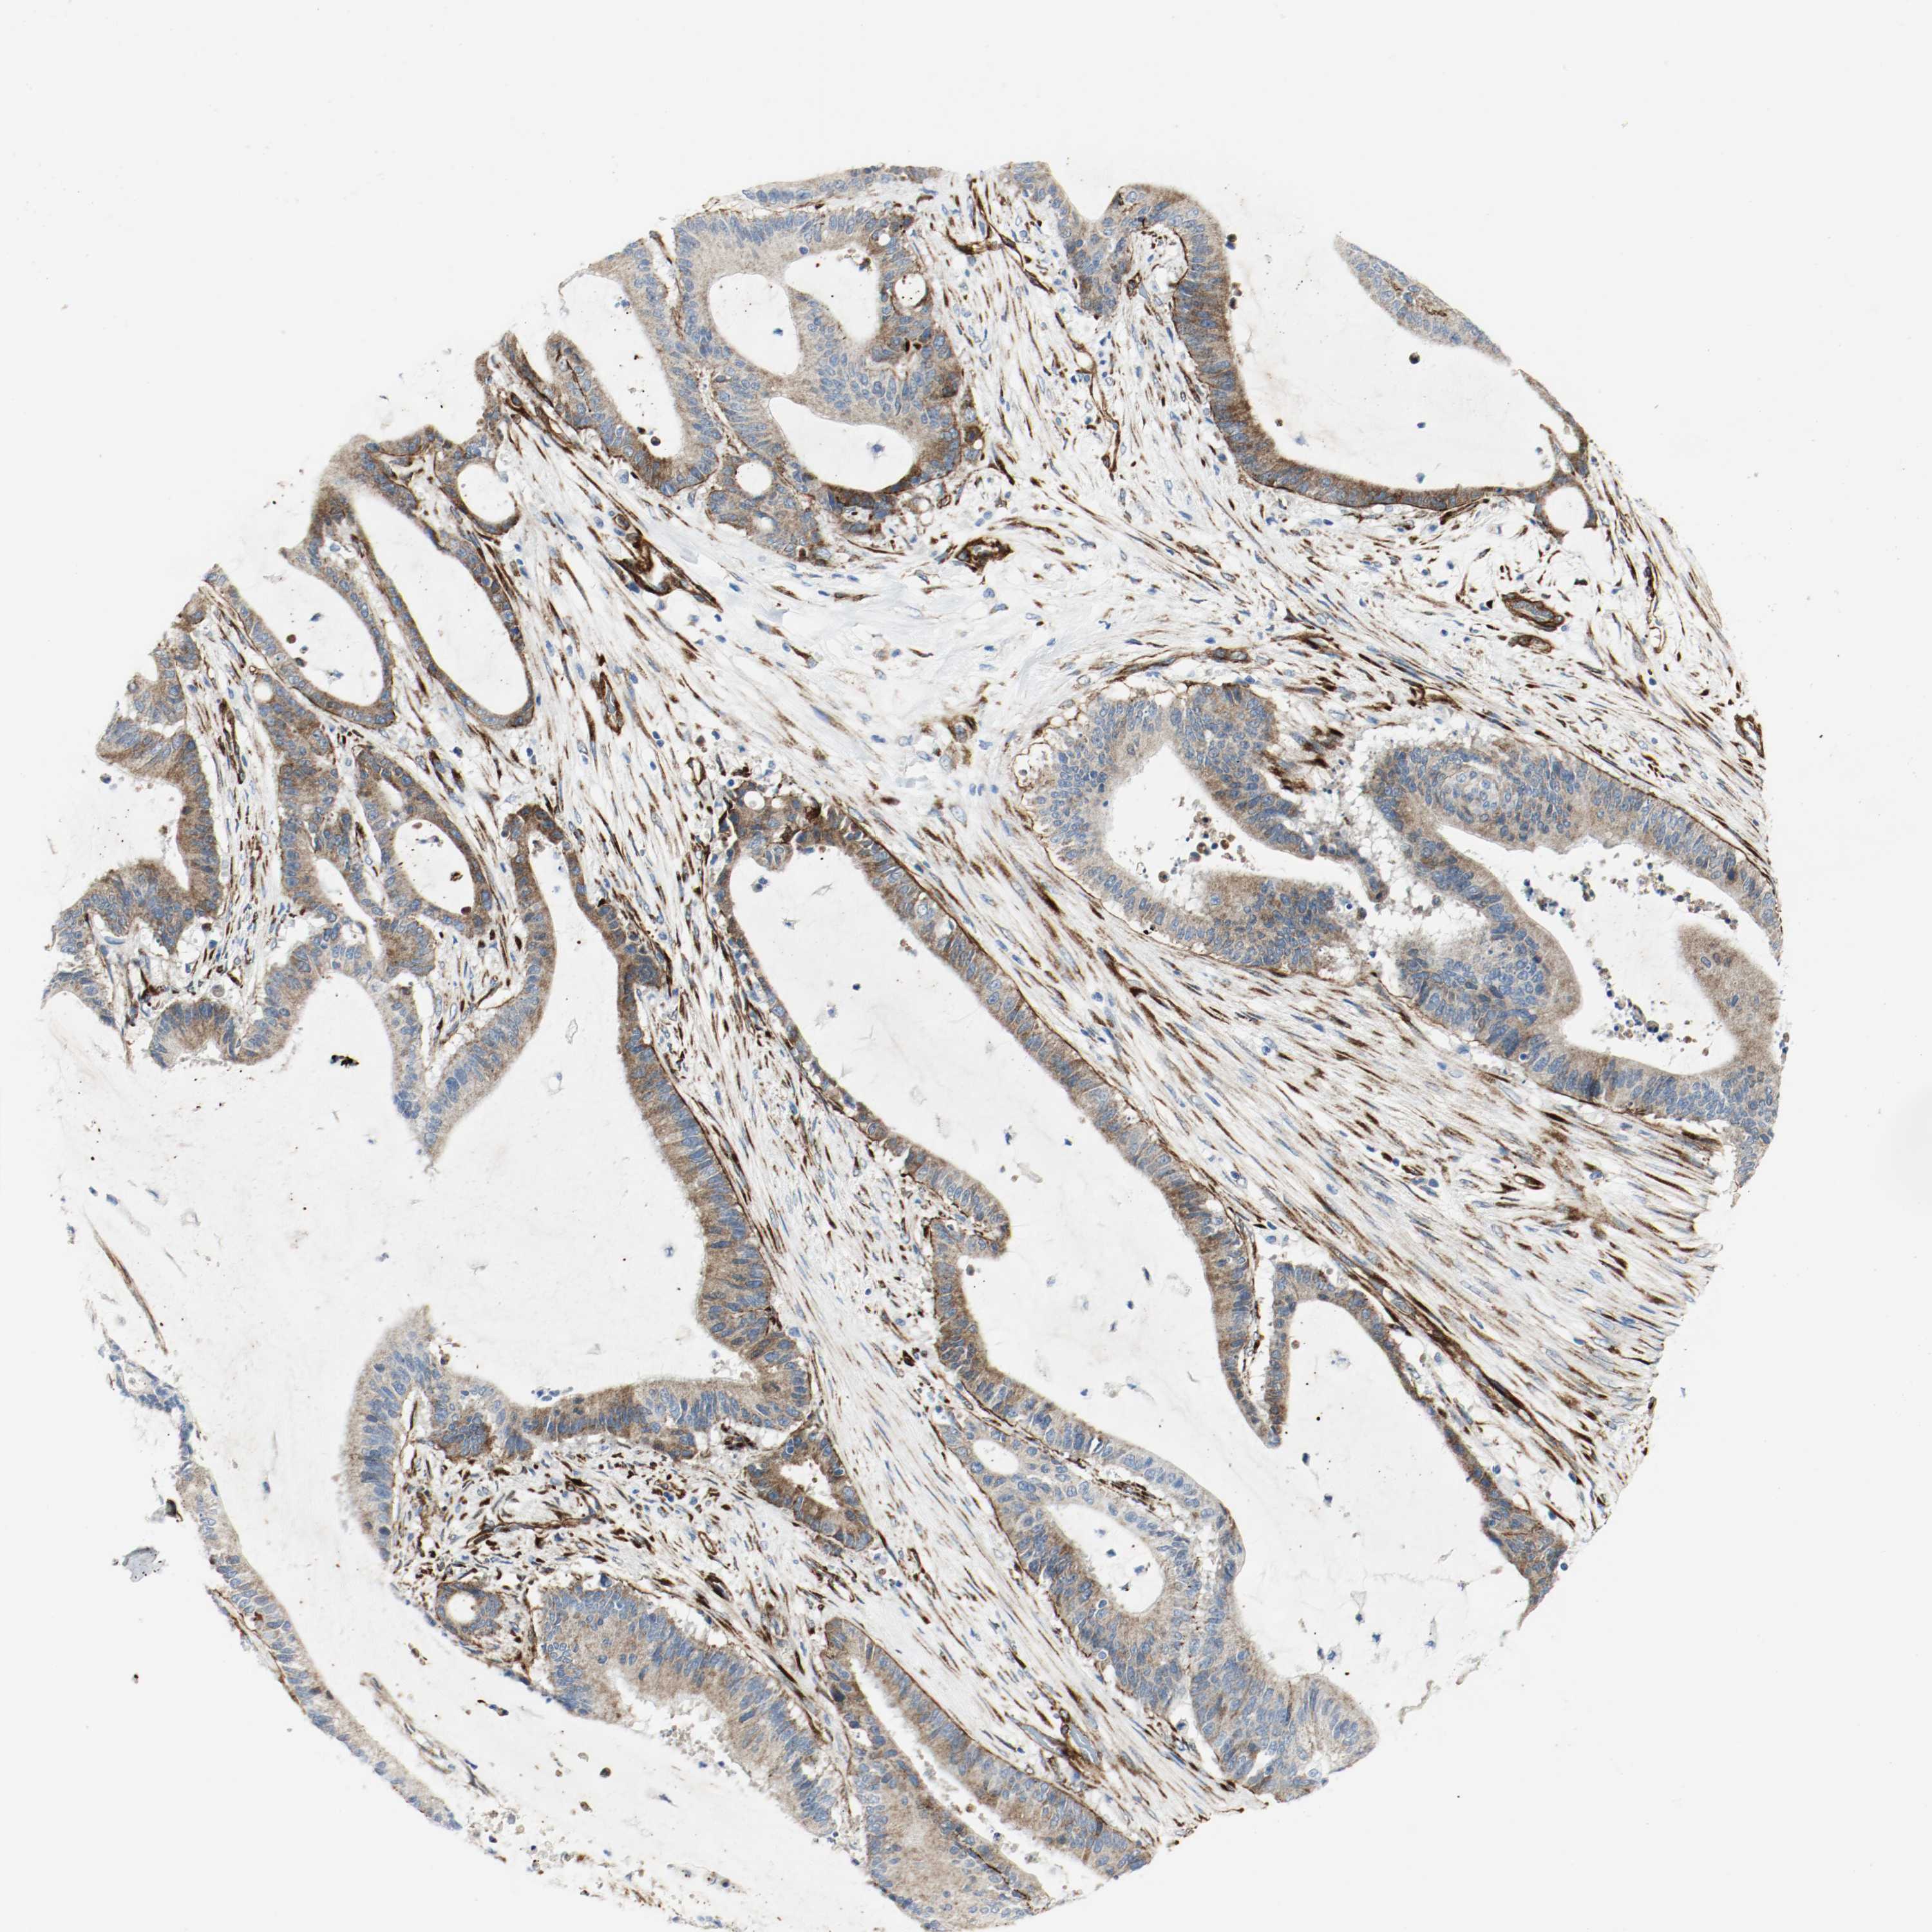

LIVER CANCER - Protein expressioni

A mouse-over function shows sample information and annotation data. Click on an image to view it in a full screen mode. Samples can be filtered based on level of antibody staining by selecting one or several of the following categories: high, medium, low and not detected. The assay and annotation is described here.

Note that samples used for immunohistochemistry by the Human Protein Atlas do not correspond to samples in the TCGA dataset.

Antibody stainingi

Antibody staining in the annotated cell types in the current human tissue is reported as not detected, low, medium, or high, based on conventional immunohistochemistry profiling in selected tissues. This score is based on the combination of the staining intensity and fraction of stained cells.

Each image is clickable and will lead to virtual microscopy that enables deeper exploration of all samples and also displays staining intensity scores, fraction scores and subcellular localization as well as patient and tissue information for each sample.

Antibody HPA004056

Antibody HPA004132

Antibody CAB004256

Staining

High

Medium

Low

Not detected

Intensity

Strong

Moderate

Weak

Negative

Quantity

>75%

75%-25%

<25%

None

Location

Nuclear

Cytoplasmic/membranous

Cytoplasmic/membranous,nuclear

Cholangiocarcinoma

Carcinoma, Hepatocellular, NOS